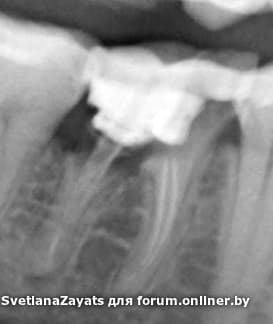

Подскажите, на зуб на снимке возможно поставить коронку или только удаление?

удалять с одномоментной имплантацией, что бы не пилить живые зубки.